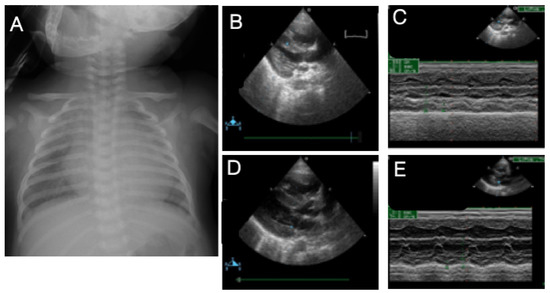

3.7. Case 7